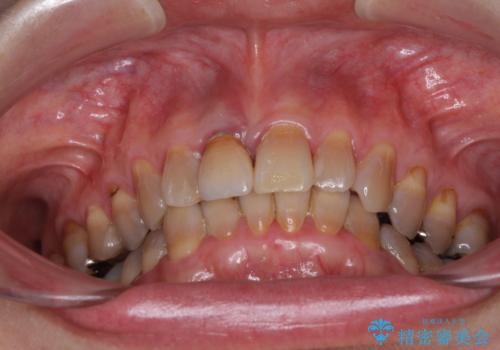

- 前歯のデコボコと、顎に負担のかかる歯並びを改善したいとのことで来院された患者様です。

うまく歯ぎしりができず、強く食いしばりをしてしまう咬み合わせであったため、奥歯に非常に負担がかかっていました。

インビザラインを用いて前歯のデコボコを改善するとともに、奥歯の咬み合わせを変えてスムーズに歯ぎしりできるように排列していくこととしました。